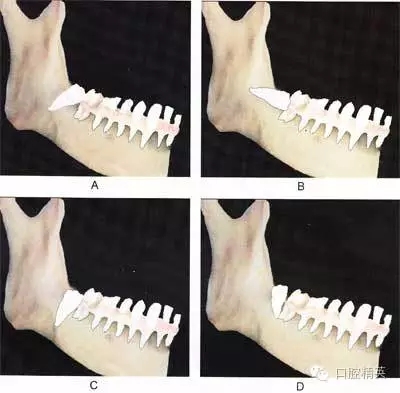

圖⒍1 根據(jù)第三磨牙牙體長軸與第二磨牙牙體長軸所成的角度不同可分為:近中 阻生(圖A):第三磨牙牙冠向近中傾斜;水平阻生(圖B):第三磨牙與第二磨牙牙體長軸相互垂直;垂直阻生(圖C):第三磨牙牙體長軸與第二磨牙平行;遠(yuǎn) 中阻生(圖D):第三磨牙牙冠向遠(yuǎn)中傾斜

A

B

C